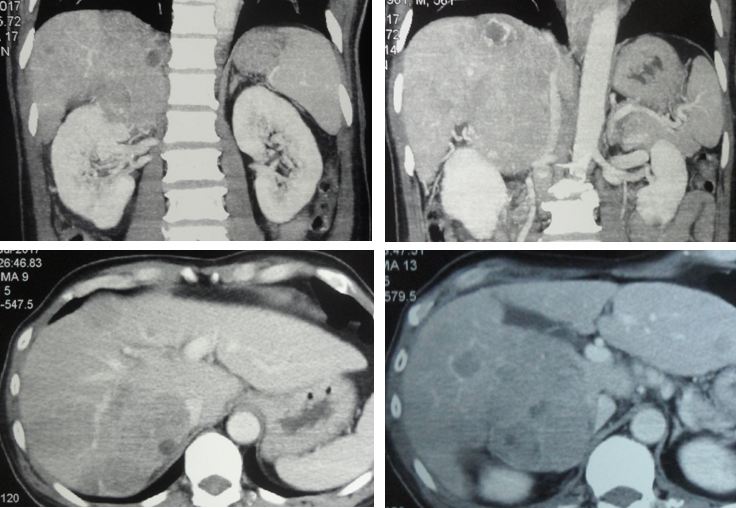

A CT scan done in a private hospital in July 2017, showed the following:

- Multiple masses in both liver lobes. The largest is about 7.5 x 8.6 x 14 cm.

- The mass compressed the inferior vena cava and the right adrenal.

- Right vocal cord paralysis.

- Mild ascites.

- Abdominal paraorta and aortocaval adeonopathy.